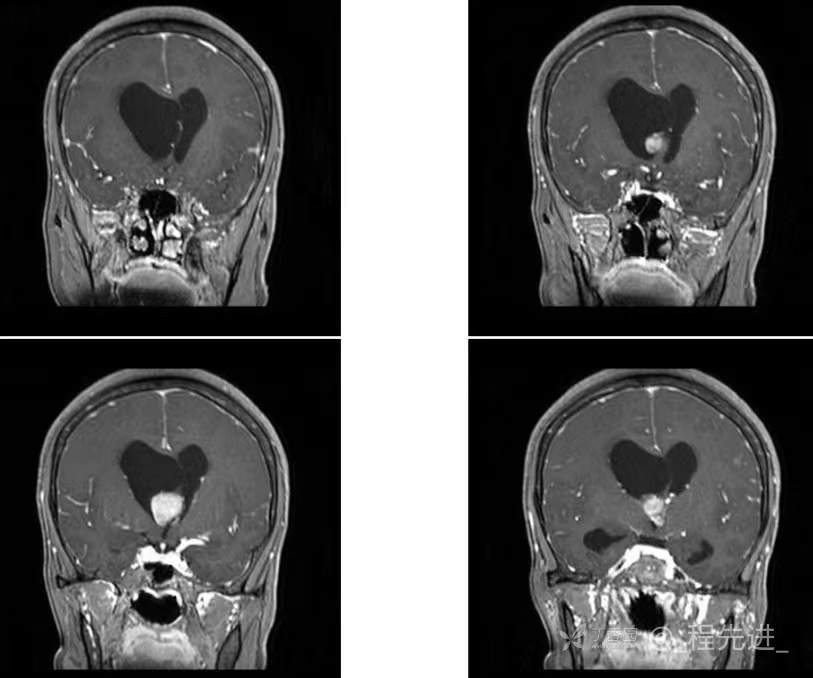

患者性别:女

患者年龄:55岁

简要病史:头痛头晕4年余,无明显诱因,10余年前因“输卵管破裂大出血”手术治疗

脑膜瘤 (78)

过渡型(混合性)脑膜瘤 (1)